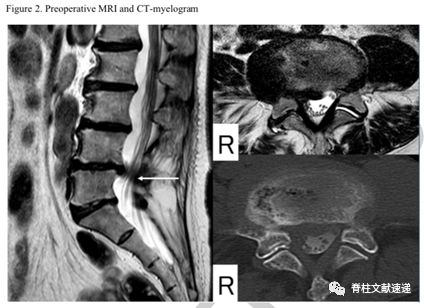

术后资料